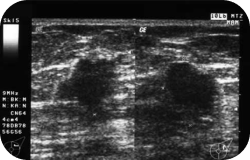

A musculoskeletal ultrasound is performed as a first-line screening modality in the evaluation of soft-tissue masses. The sonographic appearance of cysts or lipomas may obviate the need for further imaging. For other complex cystic or solid masses, this test can evaluate lesion vascularity, guide diagnostic and therapeutic aspiration or biopsy procedures, and be used for follow-up examinations to determine response to therapeutic interventions.